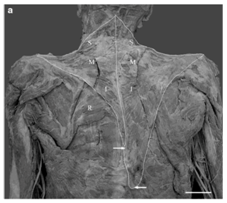

The trapezius muscle originates on the occipital bone, nuchal ligament, spinous process of the 7th cervical vertebra (C7) and all of the thoracic vertebrae (Figure 1). It has three parts. The superior portion (descending fibers) terminates on the posterior margin and superior side of the lateral third of the clavicle. The transverse portion (middle fibers) terminates on the medial margin of the acromion and superior lip of the posterior border of the scapular spine. The inferior portion (ascending fibers) ends as an aponeurosis on the posterior edge of the scapular spine and a tubercle. The trapezius muscle is innervated by the accessory nerve and the cervical plexus. It helps to move the head (extension and rotation) and the shoulders (shrugging, lowering, posterior tipping, bringing the scapulae closer together).

Figure 1 Dissection of a trapezius muscle.

Emsley et al.12 have reported a morphological anomaly found during a cadaverous dissection on a 89year-old subject. The left trapezius was significantly smaller than the right trapezius, especially in its caudal part. They also noted that the muscle fibers of the left trapezius were much lighter than on the right. Moreover, the existing fibers of the left trapezius inferior to the scapula were only one-third to two-thirds as thick as those on the right. The vertebral attachment of the inferior fibers of the left trapezius was also notably higher than that on the right. Morphometric analysis indicated that the surface area of the left trapezius was approximately 50% that of the right trapezius. In addition, the orientation of the fibers was different (Figure 2).

Figure 3 A: Digitized image of a unilaterally hypoplastic trapezius muscle on the left side.

B: Arrows indicate the approximate inferior attachment points of the left and right trapezius muscles. Note the easily visible rhomboideus major muscle (R) on the leftside. Superior (S), middle (M), and inferior (I) segments of trapezius. Scale bar 5 cm [12].